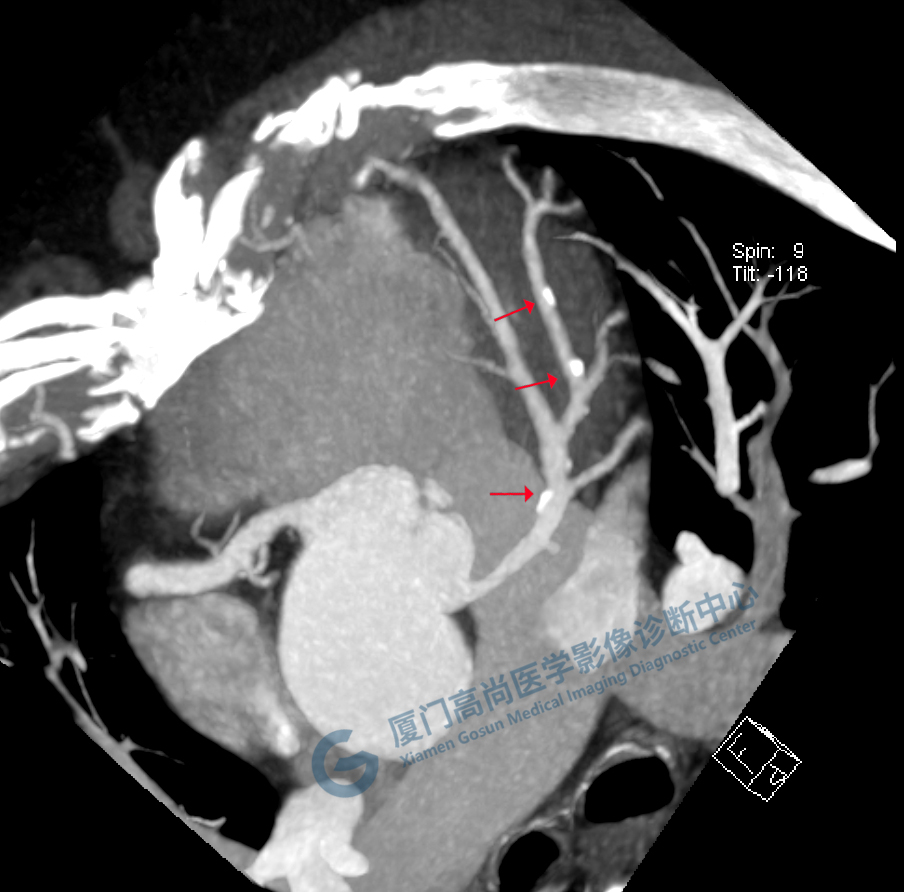

冠脈CTA圖像

左、右冠開(kāi)口

冠狀CTA右冠

回旋支

前降支

圖像所見(jiàn):左冠狀動(dòng)脈前降支,前降支近段可見(jiàn)局部鈣化斑塊,管腔狹窄約5%,左側(cè)冠狀動(dòng)脈對(duì)角支可見(jiàn)鈣化斑塊,管腔狹窄約20%-30%。

左冠狀動(dòng)脈回旋支,近段可見(jiàn)局部鈣化斑塊,管腔狹窄約5%-10%。

影像診斷:CAD-RADS分級(jí):2(25%-49%),輕度狹窄。